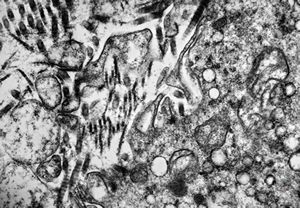

M, 43y. | myeloid leukemia … Auer bodies

M, 43y. | myeloid leukemia … Auer bodies

M, 43y. | myeloid leukemia … Auer bodies